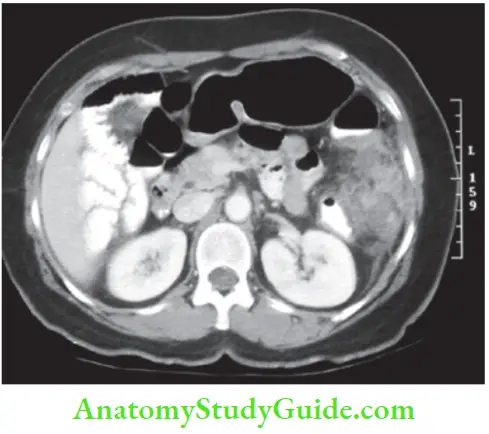

CT Scan Acute Diverticulitis:

- Can detect thick muscular folds—confirms the diagnosis.

- Detects an abscess and can confirm complications.

- Detects extraluminal air or contrast—confirms perforation.

- Can rule out other causes—acute pancreatitis with pericolic collection, etc.

- It is the investigation of choice in acute diverticulitis.

- Thickened colonic wall >4 mm.

- Pelvic abscess can be diagnosed